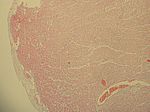

Myokarditis diphterica, HE